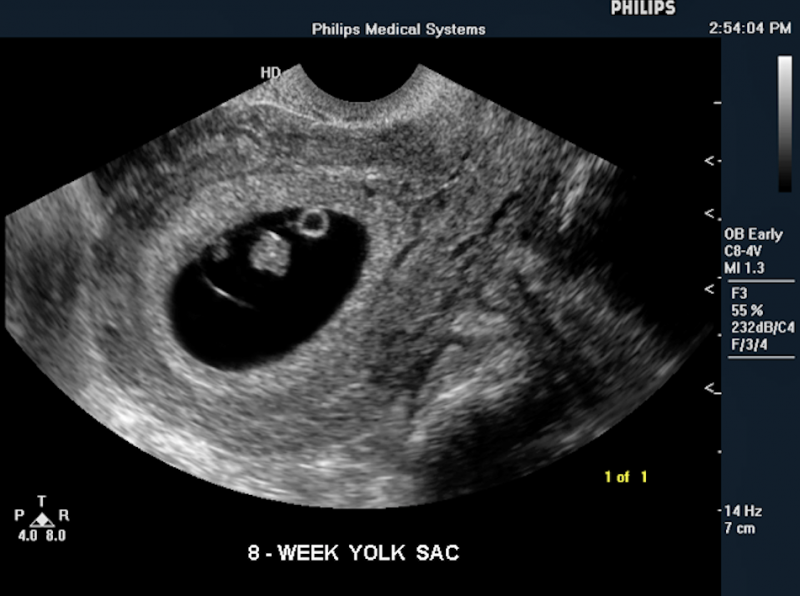

Below is a collection of prenatal ultrasound pictures from the Imaging Technology News (ITN) archive. Use the arrows to click through the image gallery. It includes transvaginal ultrasound images and fetal echocardiogram images. Fetal imaging is referred to by many names, including pregnancy sonograms, pregnancy ultrasound, endovaginal ultrasound, obstetric ultrasound, OB ultrasound, baby ultrasound, prenatal ultrasound. Fetal heart ultrasound is also called baby echo or prenatal echo.